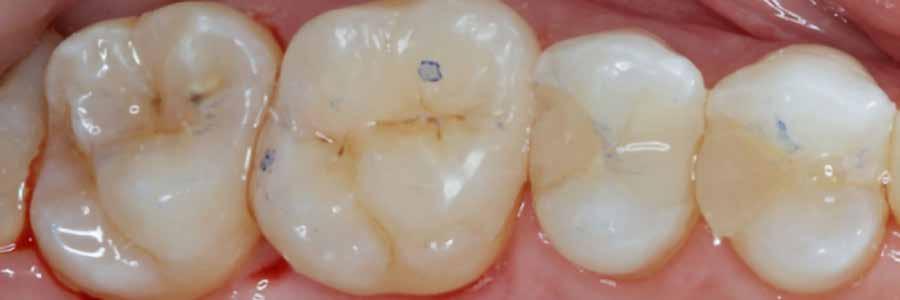

12. ábra: A premoláris fogak preoperatív állapota.

13. ábra: A premoláris fogak postoperatív fotója.